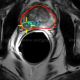

නෙදර්ලන්ත පර්යේෂණ ආයතනයක විද්යාඥයන් පිරිසක් විසින් අලුත් මිනිස් අවයවයක් සොයාගනු ලැබ තිබේ. එනම් උගුර ආශ්රිතව පිහිටා ඇති අලුත් ඛේට ග්රන්ථියකි. මෙතරම් කාලයකට...